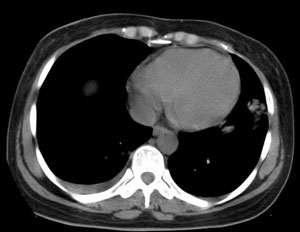

女性,30岁。

病史为胸痛20多天,无畏寒发热,无消瘦,无咳嗽咳痰。总之症状很逍遥。

临床以胸痛待查收住入院。

双肺野可见散在大小不等结节及肿块影,内密度不均匀,边缘部分清,部分欠清,纵隔未见明显肿大淋巴结.右侧胸腔少理积液.结合临床,考虑韦格肉芽肿可能吧,巨淋巴增生,结节病,特殊感染都要考虑.转移瘤临床不象.

本病例特点如下:

1.青年女性,以胸痛20多天就诊,无呼吸道及感染临床症状体征,无原发肿瘤病史;

2.肺ct表现为两肺多发大小不等结节影,大结节位于肺尖部,小结节多位于肺外带胸膜下,大结节内可见支气管充气征,周围可见月晕征(指在结节状或肉芽肿样病灶周围呈环形磨玻璃影),右肺门及腔静脉后可见小淋巴结,右侧胸腔内少量液体。

两肺散在分布大小不等的肿块及结节影,边缘毛糙,有分叶、毛刺,病灶密度不均匀,可见支气管充气相与空泡征。病变大多位于胸膜下,可见胸膜凹陷及胸腔积液。气管腔静脉间可见小结节影。

病人临床仅为胸痛,暂不考虑感染性病变。

考虑多发结节型细支气管肺泡癌。